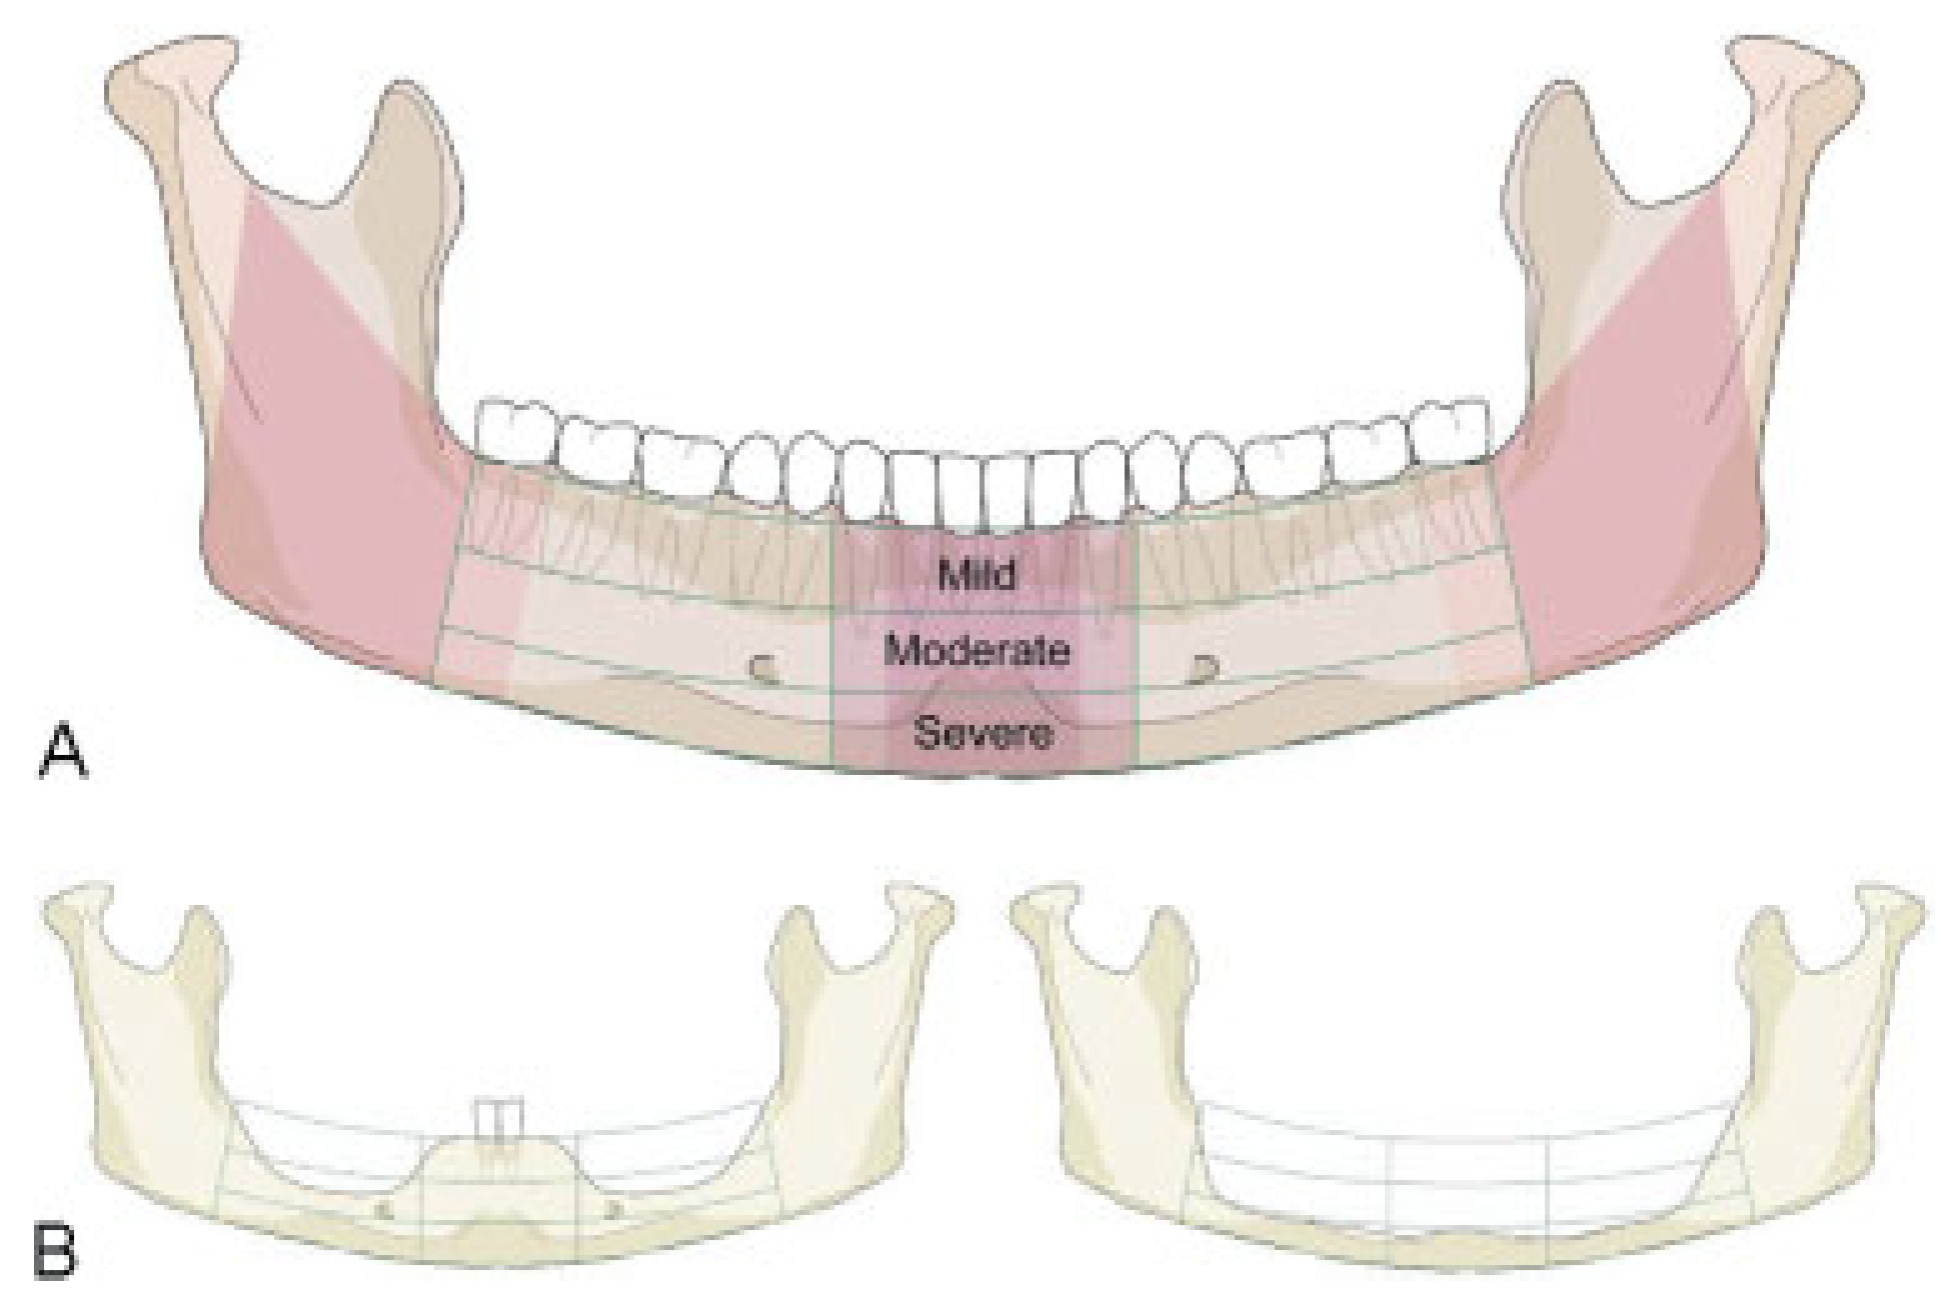

Figure 3.

Illustration of mandibular edentulism and atrophy. (A) "Atrophy grid" superimposed on a fully dentulous mandible with permanent teeth. The mandibular body regions, the para–symphsis and the transitional zones depicted as vertical sectors are maintained unchanged. To allocate the fractures to a topographical site the borderlines/frontiers of the region are transferred to the edentulous situation. (B) Left side: Moderate level of atrophy (code 2) on both the body regions, but no atrophy (code 0) in the parasymphysis. Right side: Severe level of atrophy (code 3) over the whole arch of the edentulous mandible ("pencil bone").